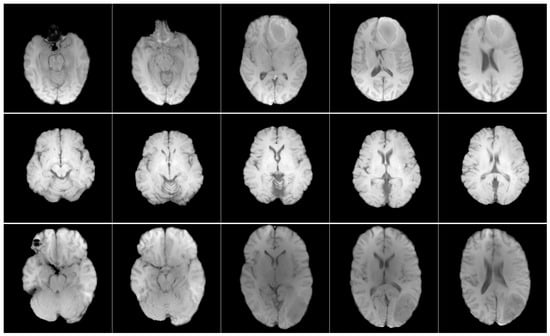

EGD is a valuable resource for neuro-oncology research, representing one of the most comprehensive multicenter collections. It contains preoperative curated T1w magnetic resonance images (Figure 2), molecular biomarkers, and tumour segmentations from 774 patients with glioma treated at Erasmus Medical Center (University Medical Center Rotterdam) between 2008 and 2018.

Patient demographic data include 281 women, 492 men, and one patient of unspecified sex. The age distribution ranges from 19 to 86 years. However, 49 patients with age records marked with the −1 label were identified, indicating missing information. Among them, one patient had neither age nor sex data available [23]. This data set differs significantly from RSNA-MICCAI in terms of anatomical presentation, as the T1w images in EGD retain full cranial anatomy, whereas the training set consists of skull-stripped images. This contrast enables the assessment of the model’s ability to generalise across differing acquisition and preprocessing protocols. A summary of the data set characteristics is provided in Table 2.

To ensure consistency, the same predictive task identifying imaging features associated with GBM—was applied across both data sets. Although the RSNA-MICCAI data set was originally designed for radiogenomic classification based on MGMT promoter methylation, the analysis instead focused on detecting characteristic GBM visual patterns. In the case of the EGD data set, the model was evaluated by identifying cases consistent with WHO grade IV glioblastoma. Despite differences in labelling criteria and image preprocessing particularly the use of skull-stripped images in RSNA-MICCAI versus full head scans in EGD both data sets are clinically aligned with GBM detection. These variations introduced valuable diversity in the input data, allowing a rigorous assessment of the model’s ability to generalise across different anatomical and acquisition settings.

Figure 2. Axial T1w pre-contrast MRI slices from the EGD data set. Each row shows a different patient, and each column shows a different slice from the same scan.